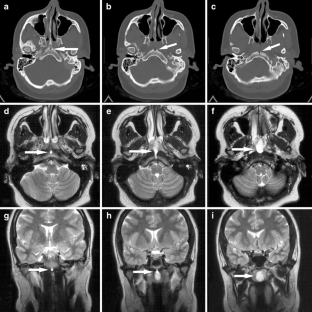

Fig. 2